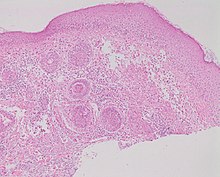

Rosacea on the face

Rosacea